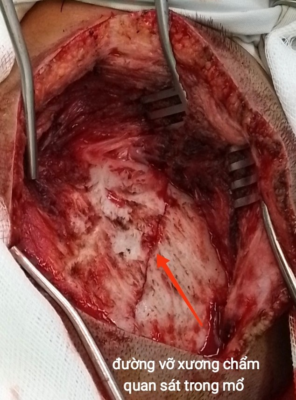

Hình 2. Hình ảnh đường vỡ xương chẩm, máu tụ trong mổ

Ca mổ diễn ra thuận lợi, lấy khối máu tụ, giải phóng chèn ép tiểu não. Kết quả Ctsccan sau mổ sạch máu tụ.

BN được phẫu thuật cấp cứu, khoan sọ, lấy máu tụ ngay sau khi có kết quả chẩn đoán và các xét nghiệm cận lâm sàng cần thiết.